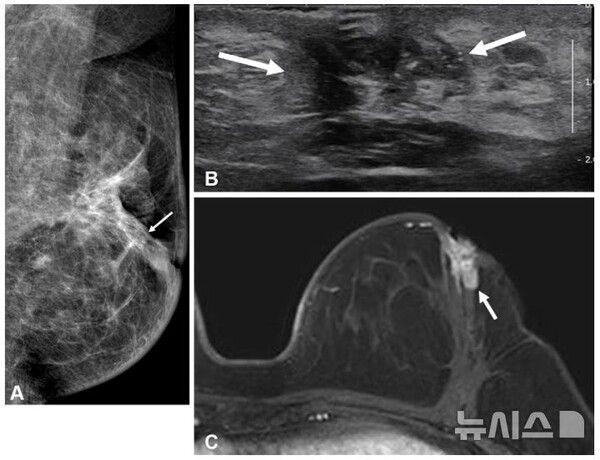

사진 = 뉴시스

국내 연구진이 수술 전 MRI(자기공명영상)가 50세 이하 유방암 환자의 재발 예방에 효과적이라는 사실을 규명했다.

유방 MRI는 유방암 검사 중 가장 민감도가 높아 유방촬영술과 초음파에서 놓친 종양도 탐지할 수 있다. 그러나 젊은 환자의 수술 전 MRI 검사가 장기적 예후에 미치는 영향, 특히 호르몬 수용체 상태에 따른 영향은 명확히 규명되지 않았다.